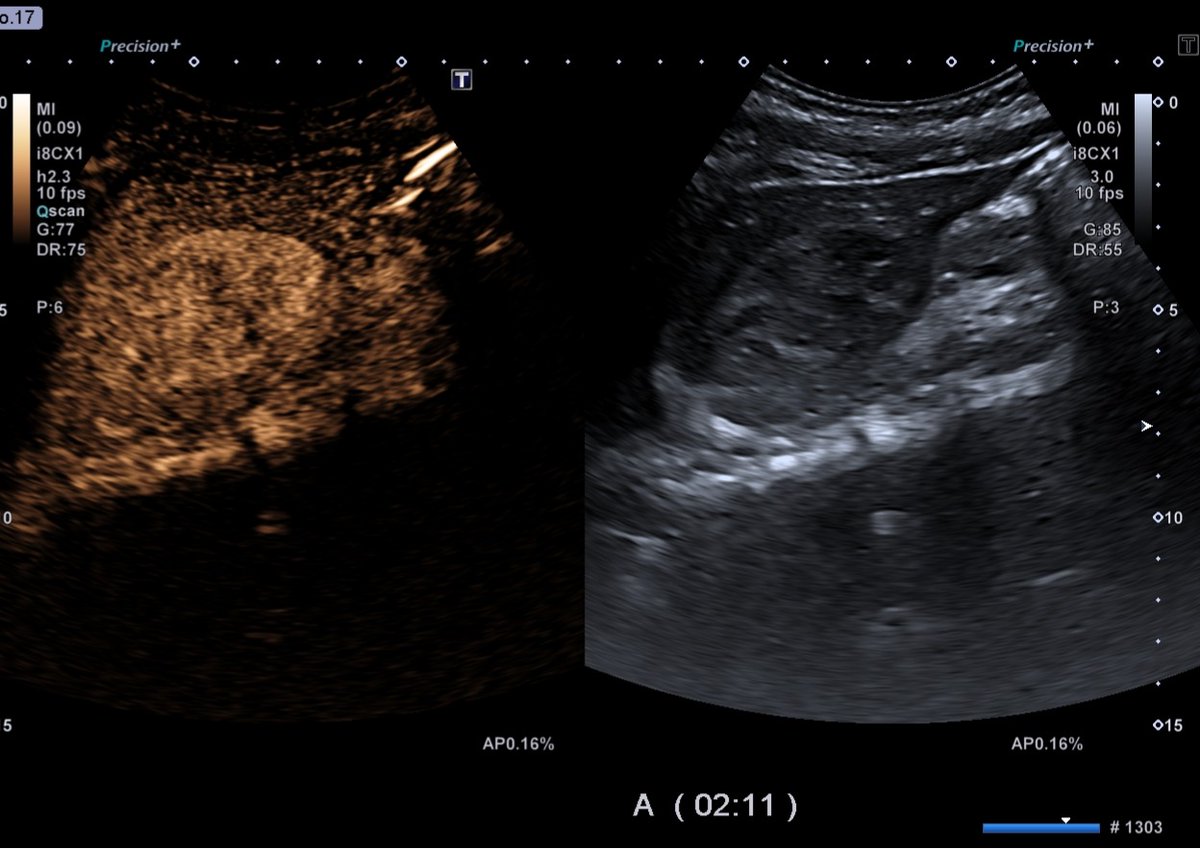

#fansecografiadigestivo 👩 45 años, dolor abdominal cólico👉 descartar colelitiasis? Ecografía: colelitiasis, LOE en LHI: heterogénea (iso-hipoecogénica), 40x50 mm, definida. No Doppler Según📋guías #EFSUMB (Dietrich CF et al. 2020) Hacemos eco con contraste

#fansecografiadigestivo

👩 45 años, dolor abdominal cólico👉 descartar colelitiasis?

Ecografía: colelitiasis, LOE en LHI: heterogénea (iso-hipoecogénica), 40x50 mm, definida. No Doppler

Según📋guías #EFSUMB (Dietrich CF et al. 2020)

Hacemos eco con contraste

#fansecografiadigestivo FASE ARTERIAL: Realce periférico nodular FASE PORTAL: Relleno centrípeto, progresivo, parcial o completo FASE TARDÍA: Realce tardío, áreas no realzadas (trombosis/fibrosis) 🏥👉HEMANGIOMA

FASE ARTERIAL: Realce periférico nodular

FASE PORTAL: Relleno centrípeto, progresivo, parcial o completo

FASE TARDÍA: Realce tardío, áreas no realzadas (trombosis/fibrosis)

🏥👉HEMANGIOMA